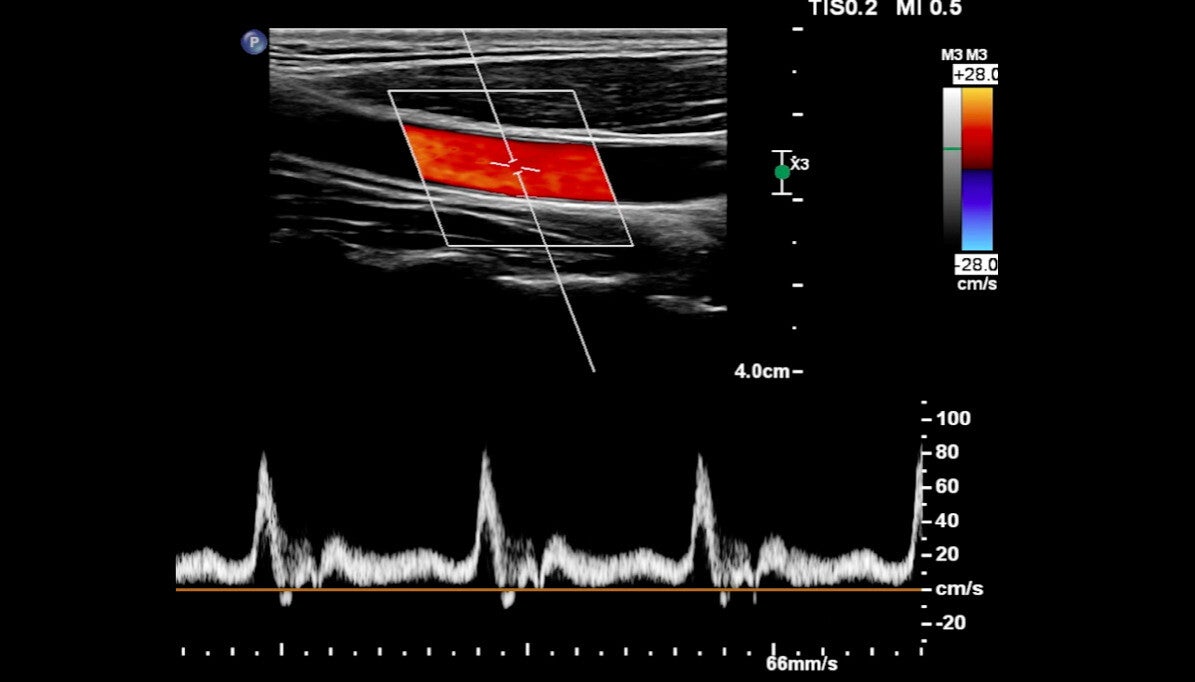

Offriamo servizi di ecografia, ecocolordoppler e valutazione del benessere cardiovascolare.

Ecografia Cilento è un servizio specializzato nella diagnostica per immagini e nella prevenzione delle malattie cardiovascolari, svolto su Appuntamento a Sapri e a Domicilio nel Cilento, nel Golfo di Policastro, nel Vallo di Diano, nella provincia di Potenzae Cosenza limitrofa.

Offriamo una vasta gamma di ecografie ed ecocolordoppler per rispondere a tutte le esigenze dei nostri clienti. La nostra missione è fornire un servizio eccellente, combinando l'alta tecnologia con la comodità di appuntamenti flessibili e visite a domicilio. Crediamo che la salute sia un diritto di tutti e ci impegniamo a rendere i nostri servizi accessibili e convenienti.